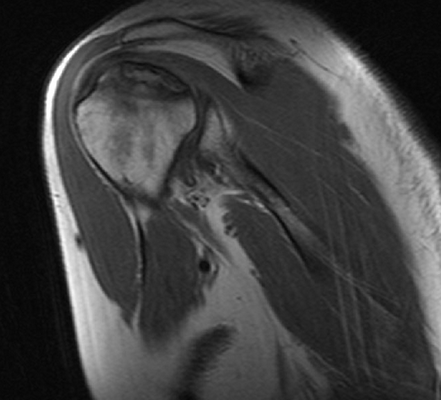

Что видно на МРТ плечевого сустава

В ходе МРТ плечевого сустава врач оценит все основные структуры области плеча: сустав, акромиально-ключичное сочленение, ротаторную манжетку, мышцы и сухожилия. Особое внимание диагност будет обращать на:

- Каковы взаимоотношения в суставе - изменена ли форма и положение головки плечевой кости, однородность ее структуры.

- Суставная щель равномерна и не расширена, смежные суставные поверхности имеют четкие и ровные контуры.

- Хрящевое покрытие равномерно по толщине и интенсивности сигнала.

- Субхондральные костные структуры не изменены.

- В полости плечевого сустава, преимущественно в полости аксиллярного кармана, определяется выпот, синовиальная оболочка не утолщена.

- Отмечается скопление жидкости в полости субакромиальной и субдельтовидной синовиальных сумок.

- Хрящевая губа прослеживается отчетливо и структура ее однородна.

- Плечелопаточные связки не деформированы.

- Щель акромиально-ключичного сочленения равномерна и не расширена.

- Клювовидно-акромиальная и клювовидно-ключичные связки хорошо дифференцируются. Сухожилия подлопаточной мышцы утолщены и разволокнены и не деформированы. Структура тканей мышц не имеет признаков фиброзно-жировой дегенерации.

- Сухожилие длинной головки бицепса равномерно по толщине и интенсивности сигнала, располагается в межбугорковой борозде, определяется на всем протяжении.